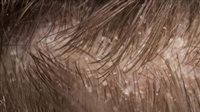

قشرة الرأس حالة جلدية شائعة، حيث يتساقط الجلد المتقشر من فروة الرأس، وتحدث القشرة الرطبة عندما يتفاعل الزهم الزائد مع الملاسيزية، وهي خميرة موجودة بشكل طبيعي في فروة الرأس، مما يتسبب في نمو الخميرة بشكل مفرط.

إلى جانب القشور الصفراء الزيتية على فروة رأسك وفي شعرك، يمكن للقشرة الرطبة أن تسبب الحكة أو الاحمرار أو التهيج، وقد تكون الأعراض خفيفة أو شديدة، وقد تظهر وتختفي، وقد تتفاقم مع التغيرات الهرمونية، أو التوتر، أو الطقس البارد والجاف.

الغدد الدهنية هي هياكل صغيرة في الجلد تفرز الزهم، وهو نوع من الزيوت الواقية للجلد، ويمكن أن تُنتج الغدد الدهنية المفرطة النشاط زيوتًا زائدة، مما يؤدي إلى ظهور قشرة الرأس الرطبة، ومن أكثر أسبابها شيوعًا فرط نمو خميرة الملاسيزية والتهاب الجلد الدهني.

الملاسيزية هي خميرة تعيش على الجلد كجزء من ميكروبيوم الجسم الطبيعي، وعندما يزداد إنتاج الزيت، فإن ذلك يشجع الخميرة على التكاثر بشكل مفرط، مما يسبب تهيج فروة الرأس وتقشر الجلد.